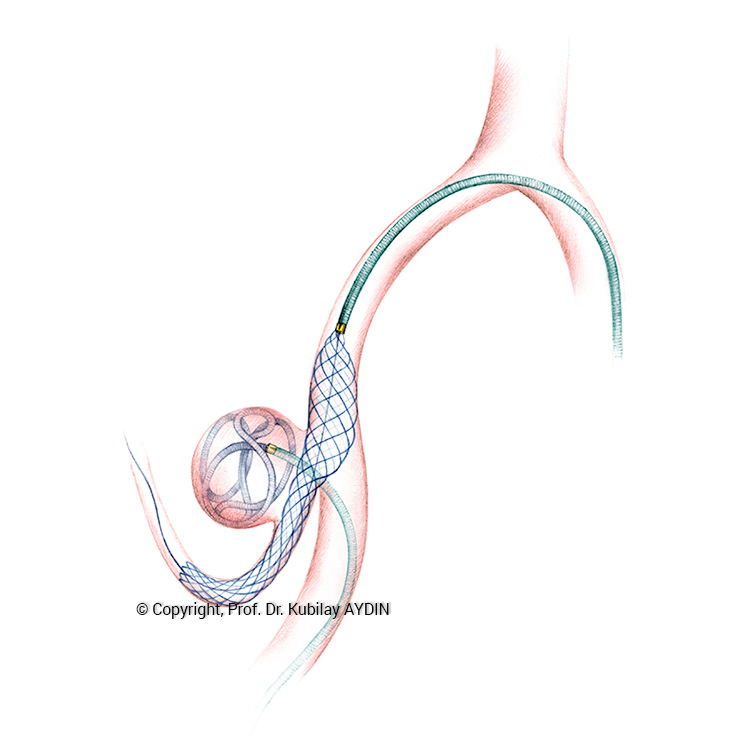

Geniş boyunlu anevrizmaların stent kullanılarak koillerle kapatılması işlemine “stent-yardımlı koilleme” adını veriyoruz. Bu işlemin ilk aşamasında anevrizmanın boynunu örtecek şekilde damar içine bir metal kafes (stent) yerleştirilerek, bir sonraki aşamada anevrizma kesesi içine konulan koillerin damar içine sarkması önlenir. Yani, burada stentin görevi, anevrizma içine doldurduğumuz koil adı verilen tellerin, damar içine sarkmasını önlemektir. Stent-yardımlı koilleme, geniş boyunlu anevrizmaların kapalı yöntemle tedavisinde tercih edilen bir yöntemdir.

Stent yardımlı koilleme tekniği ile anevrizma tedavisinde, anevrizmanın yerleştiği atardamar içerisine stent açılması için bir kateter yerleştirilir. Eş zamanlı olarak, anevrizma kesesi içerisine koilleme amaçlı farklı bir kateter yerleştilir. Damar içerisine bir stent açıldıktan sonra, anevrizma içerisideki kateterden gönderilen platinden yapılmış çok yumuşak yapıda koillerle anevrizma kesesi doldurulur. Stent, anevrizma içeriside bırakılan koillerin damar içine sarkmasına engel olur. Koilleme işlemine, anevrizma koillerle tamamen doldurulana ve anevrizma içine kan girmeyene kadar devam edilir.